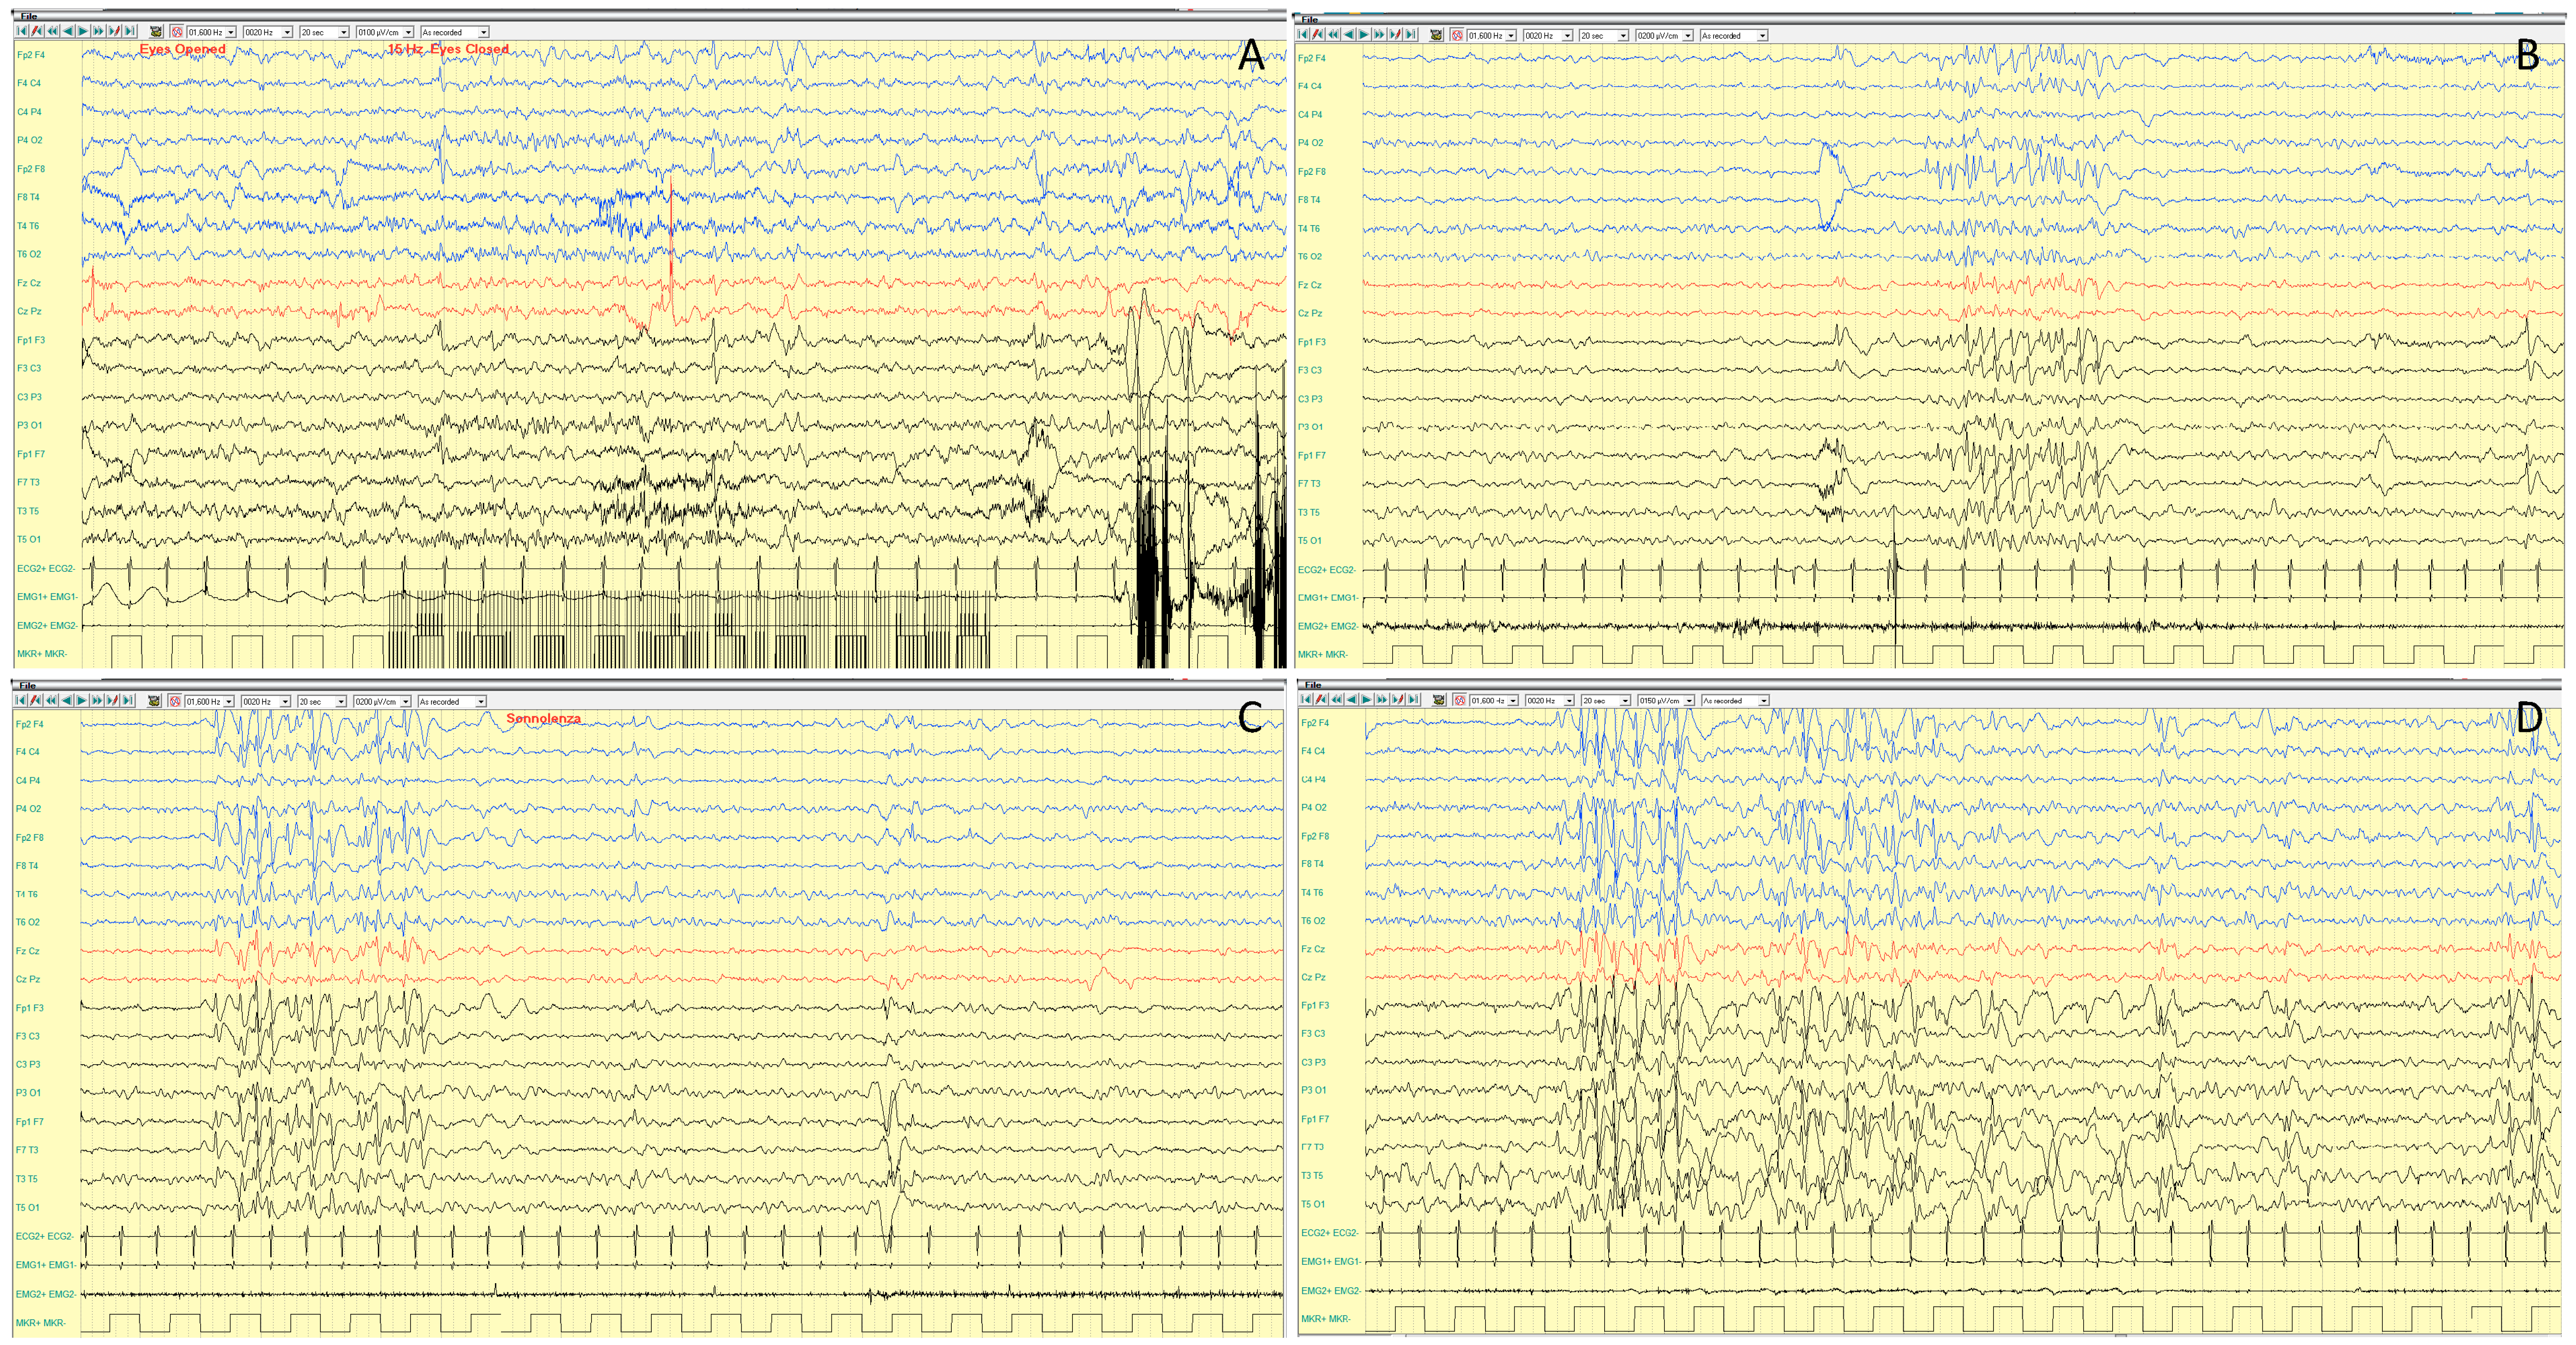

4.1.3. EEG Features

4.1.4. Neurocognitive Profile and Other Disorders